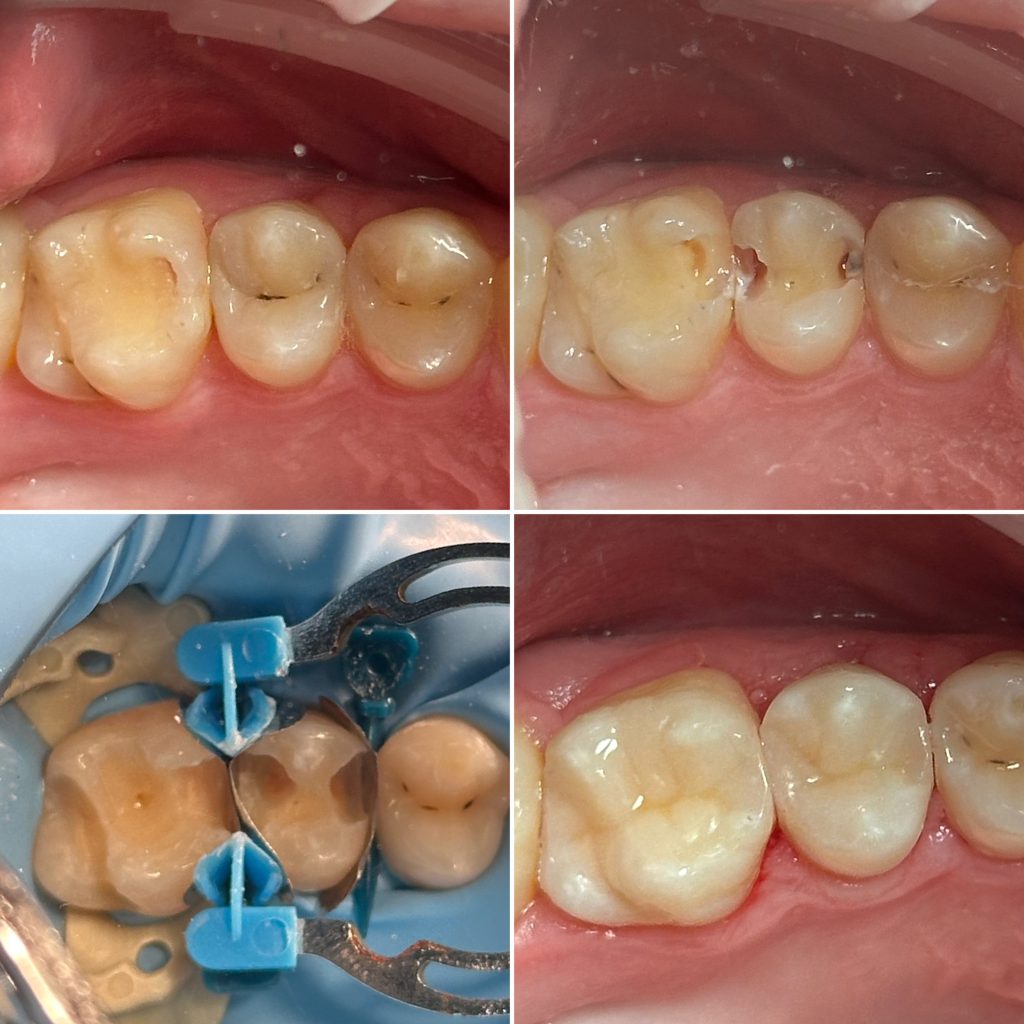

• Диагностика и лечение кариеса и его осложнений (пульпиты, периодонтиты)

• Художественная реставрация фронтального и бокового участка зубов